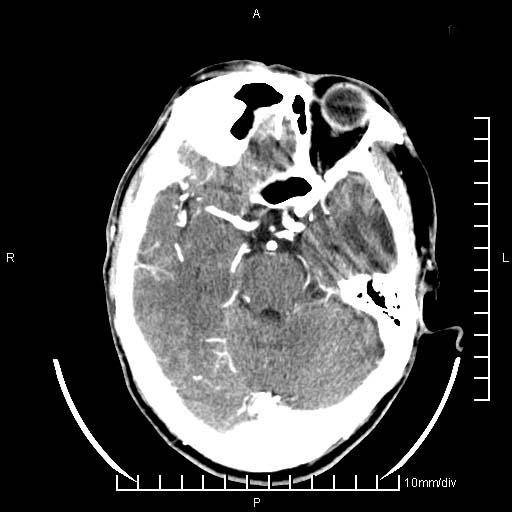

临床以双下肢浮肿,疼痛收治,无明显神经系统症状,既往无梗塞,出血病史。左颞叶见低密度灶,考虑什么?

考虑左侧颞叶脑软化灶。

无强化 无占位 软化灶吧

无强化、 无占位、局部脑沟增宽, 软化灶吧。